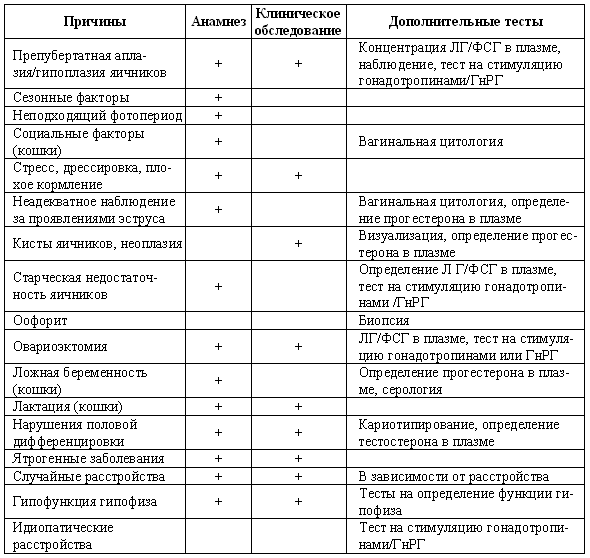

Нарушения, характеризующиеся отсутствием эструса

Анэстрия может проявиться следующим образом: либо у самки в соответствующем возрасте не началась циклическая активность, либо увеличена продолжительность интер-про-эструса (т. е. более 12 месяцев для сук и более 20 дней для кошек), либо прекратилась циклическая активность. Патология обусловливается отсутствием явных признаков проэструса и эструса или структурными либо функциональными нарушениями в системе гипоталамус-гипофиз-яичники.

Дифференциальная диагностика

Препубертатная анэстрия. Пубертат у собак наступает обычно в возрасте 6–24 месяцев, а у кошек — около 10 мес. Половое созревание связано с определенной массой тела и происходит приблизительно через 2 месяца после достижения 70–80 % от веса взрослого животного. Иногда вступления суки в пубертат можно ждать до 2–3-летнего возраста, а у грейхаундов — даже до 4- или 5-летнего возраста.

Табл. 3.1. Определение фазы репродуктивного цикла и некоторых патологий репродуктивного тракта по проявлению активности эстрогенов (определяется по вагинальной цитологии) и концентрации прогестерона в плазме

+ присутствует; — отсутствует

Аплазия/гипоплазия яичников. Врожденное отсутствие или недоразвитие одного или обоих яичников наблюдается редко. Характерным признаком является повышение концентрации гонадотропинов в плазме в связи с недостаточностью ингибирующего воздействия гормонов яичников на гипоталамо-гипофизарную активность. В случае односторонней (но не двусторонней) аплазии стимуляционный тест с ГнРГ выявляет ответное повышение концентрации эстрадиола. Лапаротомия обнаруживает недоразвитые яичники или их отсутствие.

Сезонность цикла. Половой цикл домашней собаки (за исключением африканских пород, т. е. бассенджи) не имеет сезонного характера. Дикие собаки (динго, волки) спариваются осенью. При естественном освещении брачный сезон у кошек продолжается весной, летом и осенью, а зимой наступает период анэструса. Содержание при искусственном освещении (т. е. в помещении) оказывает влияние на цикличность.

Фотопериодизм. Для нормальной циклической активности животным с сезонным брачным периодом (кошки и дикие собаки) требуется соответствующий световой режим. При неблагоприятном световом режиме, т. е. недостаточном освещении, наблюдается снижение циклической активности. Стимуляционным фотопериодом для кошек является 12–14-часовая продолжительность светового дня и 10–12-часовая — темного времени суток, хотя имеются сообщения о том, что циклическая активность сохраняется и при 10-часовом освещении (соответственно 14 часах темного времени суток).

Кошки: социальные факторы. У животных, стоящих на нижней ступени иерархической лестницы, может наблюдаться «скрытая течка». Период эструса не сопровождается соответствующим поведением, несмотря на наличие характерных эндокринных и цитологических изменений. Индикатором эструса служат вагинальные выделения, свидетельствующие о повышенном уровне эстрогенов.

Стресс, переутомление, истощение. Перечисленные факторы способны угнетать активность яичников у большинства видов животных. Активные тренировки часто являются причиной отсутствия эструса у грейхаундов. У кошек стресс может быть результатом перенаселения, экстремального температурного режима, неправильной диеты, частых выставок и связанных с ними переездов.

Неадекватное наблюдение/проявление симптомов эструса. Объясняется ошибками владельца или особенностями животного. Ошибки владельца заключаются в невнимании или непонимании особенностей эструса. Чаще всего такие ошибки наблюдаются при содержании животных во дворе, вольерах или в группе. К особенностям животного следует отнести скудные физические проявления проэструса/эструса (например, набухание вульвы у грейхаундов значительно менее выражено, чем у боксеров), наличие длинной шерсти (ньюфаундленд, самоед), отсутствие поведенческого эструса может провоцировать отсутствие интереса со стороны самцов или недостаточное возбуждение самой самки. Для выявления проэструса/эструса рекомендуется внимательное наблюдение за поведением самки, осмотр вульвы дважды в неделю и еженедельная проверка наличия вагинальных выделений. Определение концентрации прогестерона не является необходимым, поскольку этому повышению предшествует появление вагинальных выделений, объясняющееся активностью эстрогенов. Тем не менее в ходе первичного осмотра рекомендуется определить уровень прогестерона, дабы убедиться, что в течение 2 предшествующих месяцев у самки не было овуляции.